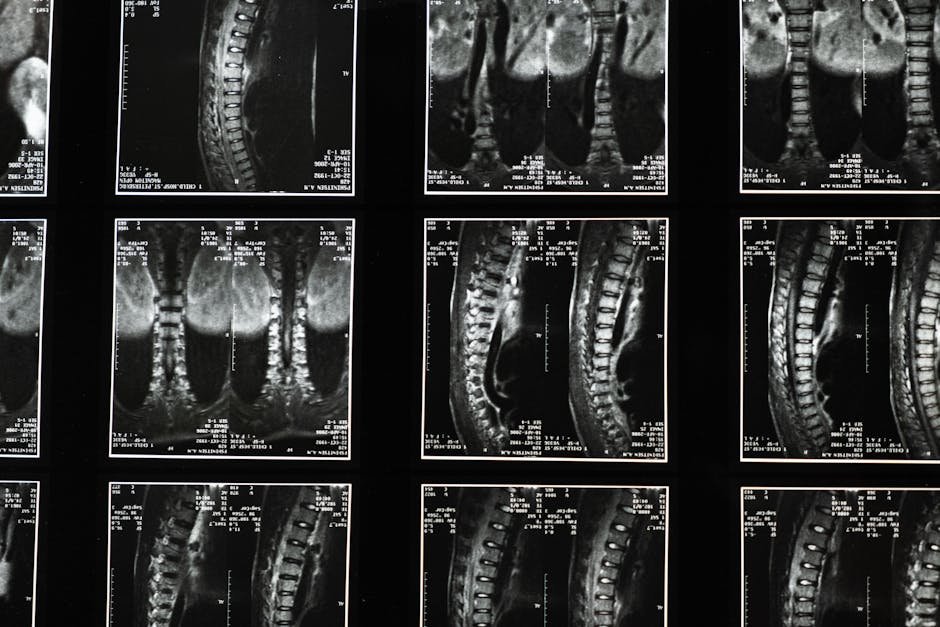

Osteoid osteoma

UBE resection completely removed a cervical osteoid osteoma

Surgeons safely remove a benign spine tumor using minimally invasive endoscopy